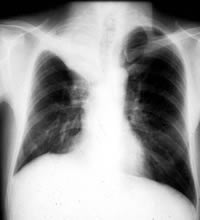

CTは断面を撮影するため、胸部X線と違って重なる部分がなく、肺のほとんどの部分を見ることができます。また肺がんの初期の淡い陰影(「すりガラス陰 影」といいます=写真2)でも写ります。これは胸部X線写真では写りません。

手術ができた患者は、半数以上が治っています。胸部X線写真で、大きさが1円玉くらいで見つかった場合、約8割の患者は手術で治ります。「すりガラス陰 影」で見つかれば、9割以上の人が治ります。早期発見ができれば、手術で治る確率は高まります。